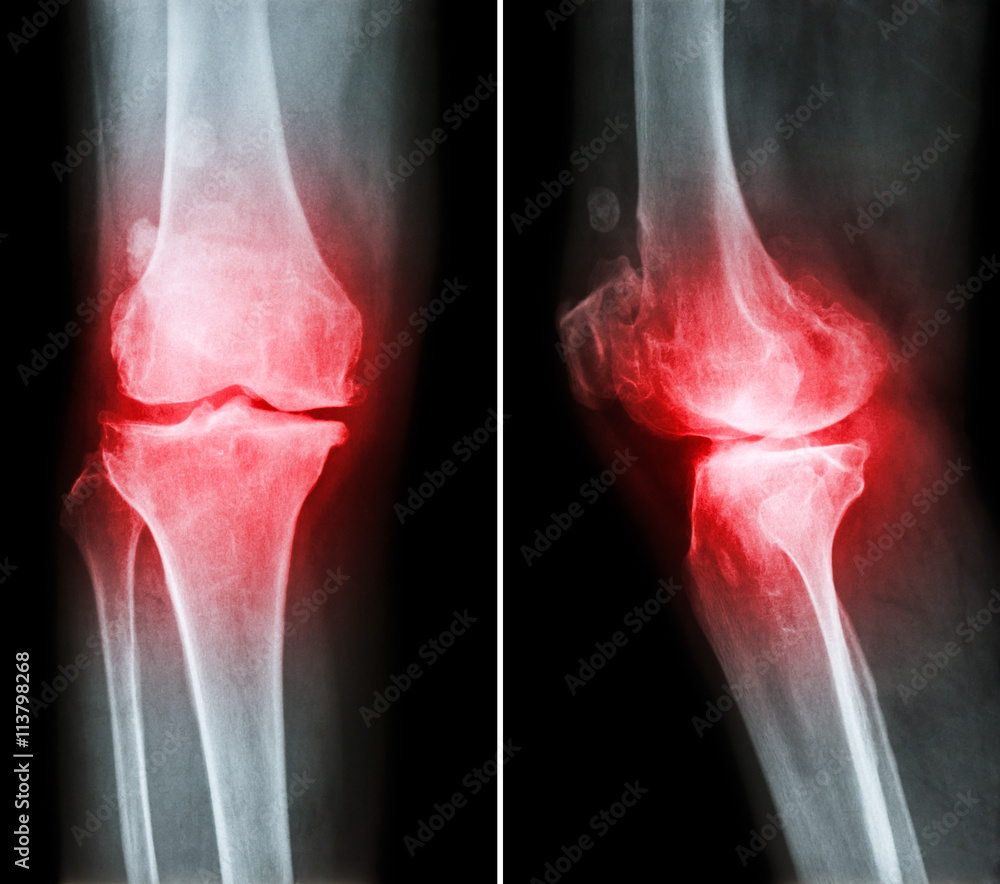

Osteoarthritis Both Knee . Film Xray AP Anterior Posterior Of Knee Osteoarthritis Bone Spur Formation The most common cause of bone spurs is joint damage from osteoarthritis or degenerative joint disease. They form when a joint or bone has been damaged by. Osteophytes (bone spurs) are bony lumps that grow on the bones in the spine or around joints. They’re extra growths of bone tissue that look like smooth. But younger adults can develop bone. Osteoarthritis Bone Spur Formation.

Osteoarthritis knee . film xray knee ( anterior posterior and Osteoarthritis Bone Spur Formation If you have osteoarthritis, a risk factor for. The most common cause of bone spurs is joint damage from osteoarthritis or degenerative joint disease. If you are overweight and have osteoarthritis of the hips or knees, weight loss may help ease bone spur pain. Bone spurs are a common side effect of aging, osteoarthritis and tissue injury. They’re extra growths. Osteoarthritis Bone Spur Formation.